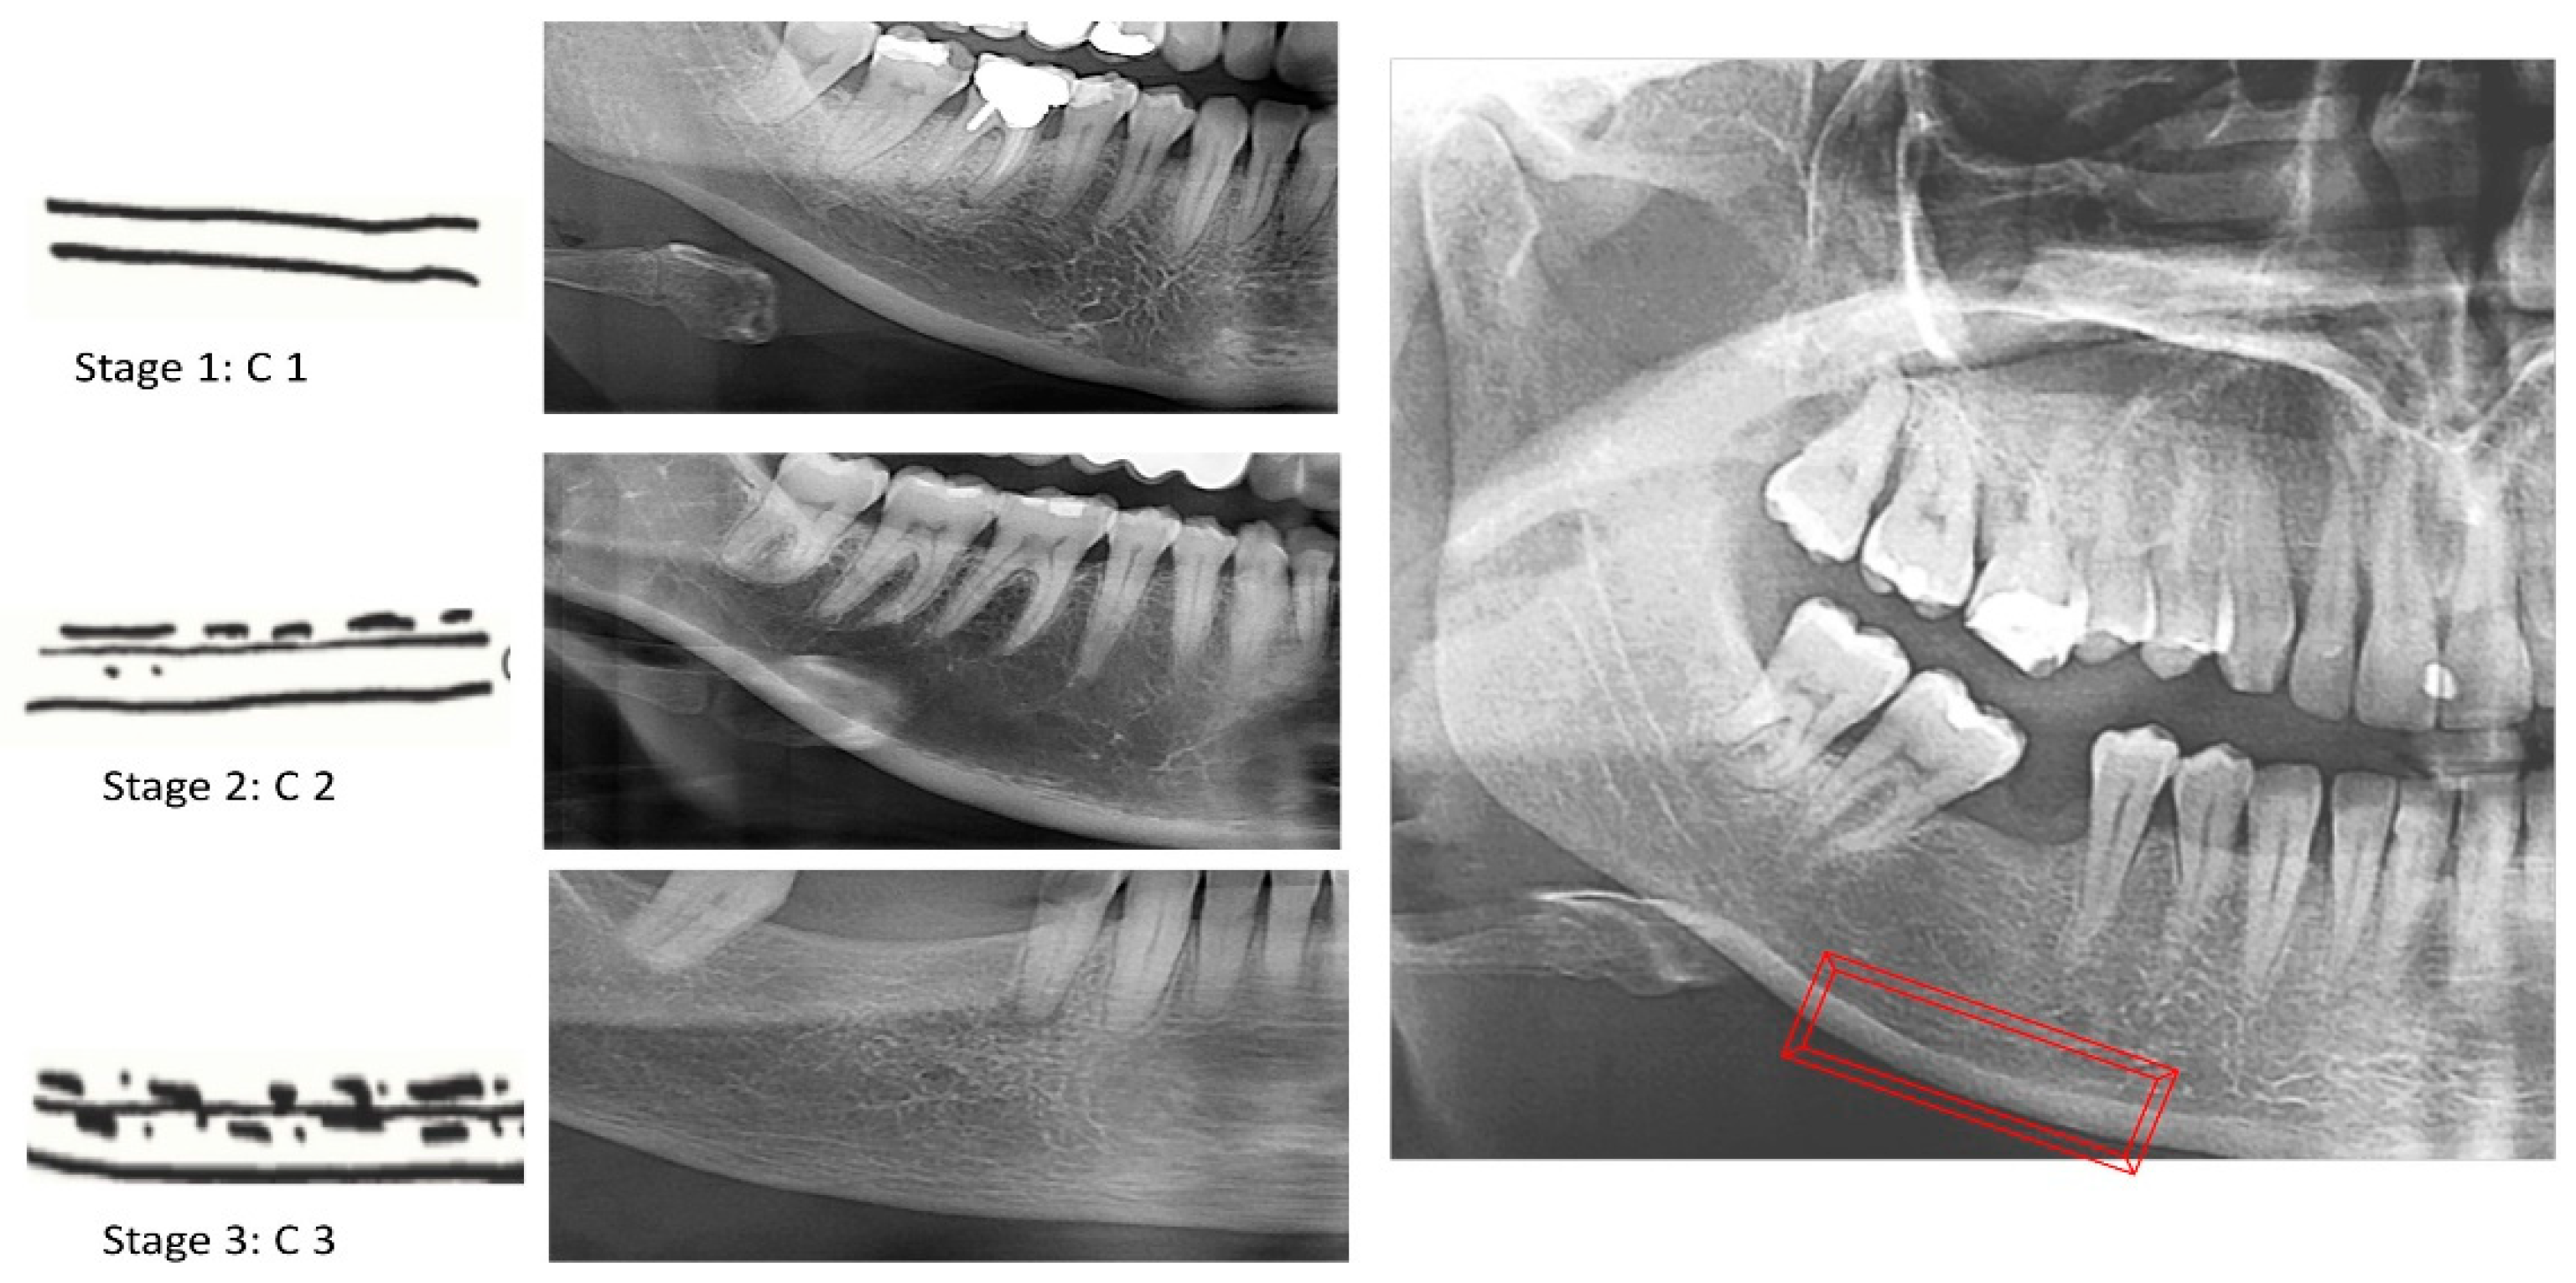

Diagnostics Free Full Text Osteoporosis Screening Using Dental